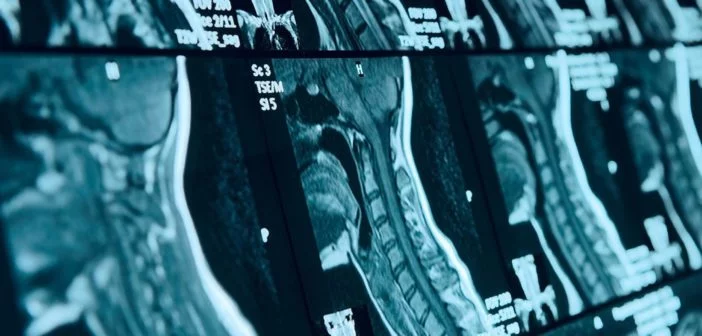

Dr. Szentágotai Attila idegsebész, klinikai főorvos tevékenységi köre:

- degeneratív eredetű gerincsebészeti betegségek: porckorongsérv, gerinccsatorna szűkület, instabilitás kezelése – dekompresszió és/vagy rögzítés hagyományos és minimalisan invazív technológiával,

- gerincsérülések: baleseti eredetű csigolyatörés, gerinccsatorna vérzés,

- gerincdaganatok: gerinccsatornán belüli és kívüli (áttétes gerincdaganat),

- porotikus (csontritkulásos) eredetű csigolyatörés: percutan (nyílt feltárás nélkül) csigolyastabilizáció csontcement alkalmazásával – vertebroplastica,

- műtéti kezelést nem igénylő, derék és alsó végtagi kisugárzó fájdalmat okozó, degeneratív eredetű gerincbetegségek percutan fájdalomcsillapító kezelése: ízületi érzéstelenítés, gerinccsatornai érzéstelenítés, szelektív idegblokád,

- gerinc- és koponya daganatok szakvizsgálata, kezelési lehetőségei, terápiás javaslata